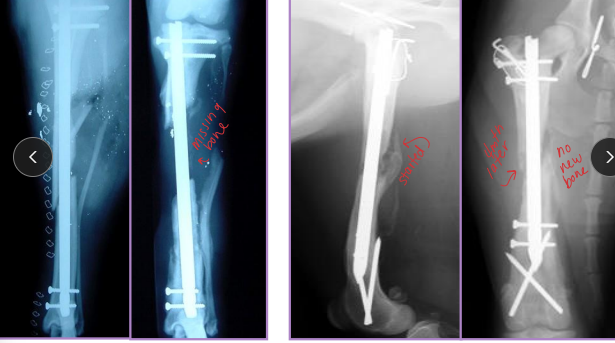

The 4 A’s of healing

Apparatus: implant integrity

Activity: evidence of bone formation/healing

Direct: fracture line becomes fuzzy

Indirect: callus

Alignment of bone

Apposition of repair

Complications of Bone Healing

Dt: Take xrays every 4-6 weeks postop** compare pre/post op

Delayed Union: Healing slower than expected, but evidence of healing present

Tx: wait, bone graft, stabilize, remove loose implants

Nonunion: No progression on rads for 3+ months, instability, poor blood supply

Vascular (viable): callus present, fracture line persists

Tx: stabilize, remove implants, align

Avascular (non-viable): little/no callus, poor biology

Tx: curettage, rigid fixation, cancellous graft, remove loose implants

Malunion: Fracture healed in abnormal alignment